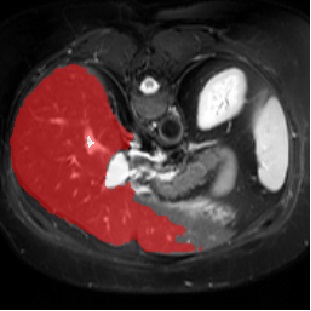

For CMR dataset, we only consider setting 1 because setting 2 is difficult to implement. The results are shown in Table 1 and Figure 4. In general, our proposed method is superior than others. For CHAOS dataset, we consider both setting 1 and setting 2. From the results, we can see the performance of our proposed model is higher than others on CHAOS and CMR datasets. Compared with Q-Net, our mean dice score on CHAOS dataset achieves about 82%. The segmentation results of the model are shown in Figure 5. In setting 2, the slices of the objects containing the test classes are all removed at training stage, and our model still performs well. As can be seen from the Table 2, the segmentation effect of the model on the right kidney is slightly worse than that of ALPNet, but overall, we achieve the best performance. The specific segmentation results are shown in Figure 6. As can be seen from the figure, other methods have excessive segmentation, but ours does not. Our segmentation results are more accurate and reduce redundant segmentation.